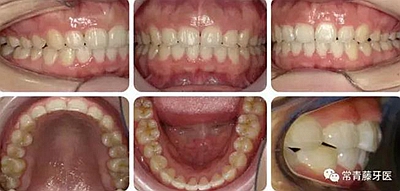

治療23個月結(jié)束。可見兩側(cè)尖磨牙達(dá)到中性關(guān)系,上下牙列排齊整平,前牙覆合覆蓋正常,中線齊。

結(jié)束3個月后復(fù)查,無明顯復(fù)發(fā)。

曲斷可見牙根基本平行。

術(shù)前術(shù)后描記圖顯示上牙列整體遠(yuǎn)移有效,表現(xiàn)為磨牙遠(yuǎn)移及上前牙內(nèi)收(黑色術(shù)前,紅色術(shù)后)。